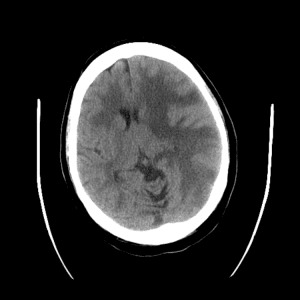

ACA and MCA territory infarct

PCA infarct

PICA infarct

Internal capsule lacunar infarct